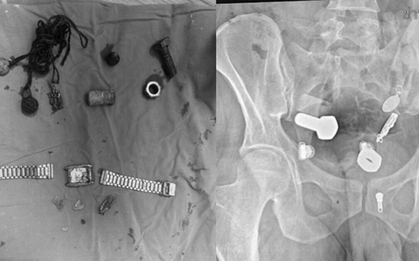

Người đàn ông 33 tuổi bỗng đau bụng dữ dội, sốt nhẹ và phản ứng thành bụng, khiến gia đình vô cùng hoảng hốt. Gia đình bệnh nhân vô cùng kinh ngạc khi biết "thủ phạm" gây ra tình trạng này.